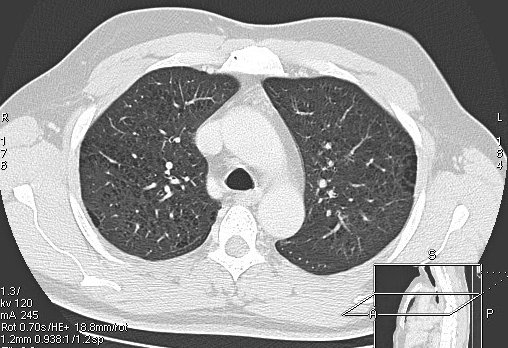

Foto: Aleksandar Ivković Foto: Aleksandar Ivković Foto: Aleksandar Ivković Strašna razlika kod pluća pušača i kovid pozitivne osobe autor: Božica Luković Zdravlje 23. jan. 2021. 12:06 > 23. jan. 2021. 12:15 0 Podeli vest: Radiolog Aleksandar Ivković od početka pandemije daje korisne informacije o svim aspektima kovida 19. On je nedavno uporedio rendgen snimke pluća zdrave osobe, pušača, osobe koja je zaražena gripom H1N1, a onda i osobe koja ima kovid 19. Razlike su zapanjujuće. Podeli vest: Oglas Objavu doktora Ivkovića sa njegovog bloga "Ljudi i ostale laži" prenosimo u celosti."Nedavno sam video u medijima da je neko preneo rdg sliku i razlike kod nalaza zdrave osobe, pušača i bolesnog od kovida 19. Kako nisam baš previše zadovoljan onim što je prikazano, evo kako to izgleda u našoj varijanti. Zdrava osoba CT nalaz kod zdrave osobe podrazumeva da ne postoje nikakvi poremećaji strukture plućnog parenhima, da su krvni sudovi uredni i da nema suženja disajnih puteva, kao i da nema uvećanih limfnih žlezda u hilusima pluća i medijastinumu. Foto: Aleksandar Ivković | Foto: Aleksandar Ivković * Foto: Aleksandar Ivković | Foto: Aleksandar Ivković Zdrava muška osoba mesec dana nakon zapaljenja pluća tokom kovida 19. Nalaz bez nekih posebnih problema iako se naziru tragovi zapaljenja. Snimak u boji je zdrava osoba, nepušač, bez ikakvih bolesti pluća u istoriji. Grip H1N1 Pokazaću samo drastične nalaze kod gripa H1N1, to je znači onaj grip koji je izazvao epidemiju španske groznice i epidemiju 2009. godine koja još uvek nije prestala (svake godine imamo makar 15%). Foto: Aleksandar Ivković | Foto: Aleksandar Ivković * Foto: Aleksandar Ivković | Foto: Aleksandar Ivković * Foto: Aleksandar Ivković | Foto: Aleksandar Ivković * Foto: Aleksandar Ivković | Foto: Aleksandar Ivković Nisu svi pacijenti imali ovakve nalaze, pokazujem one koji su imali tešku kliničku sliku. Kod gripa se sve odvija obično u sedam dana. Kao što se vidi, zapaljenje je bilo jednostrano, uglavnom. Ali kada je dolazilo do pogoršanja, onda je centralno obostrano dolazilo do edema pluća. Pušenje Kod pušača postoje razne varijante nalaza na plućima. U principu nisu tako dramatične kao što su zapaljenja. Nalaz na plućima kod pušača može biti potpuno normalan. Ovo ne pišem zato što podržavam pušenje, naprotiv, veliki sam protivnik, ali iznošenje laži nikada nije dobro. Dve dijagnoze su bitne kao posledica pušenja. Prva je hronična plućna opstruktivna bolest: Foto: Aleksandar Ivković | Foto: Aleksandar Ivković * Foto: Aleksandar Ivković | Foto: Aleksandar Ivković * Foto: Aleksandar Ivković | Foto: Aleksandar Ivković Jasna je razlika u nalazu, posebno na ovim slikama u boji, gde su ta plava polja delovi pluća koji su propali zbog cigareta (može da se uporedi sa zdravim plućima iznad).Druga bolest koja je česta kod pušača je u svakom slučaju karcinom. Foto: Aleksandar Ivković | Foto: Aleksandar Ivković * Foto: Aleksandar Ivković | Foto: Aleksandar Ivković * Foto: Aleksandar Ivković | Foto: Aleksandar Ivković * Foto: Aleksandar Ivković | Foto: Aleksandar Ivković Tkivo koje raste unutar pluća i razjeda ga. Takav je nalaz kod karcinoma pluća. Često je uzrok upotreba cigareta. Kovid 19 O kovidu sam pisao puno puta. Evo nekih slika, radi poređenja. Foto: Aleksandar Ivković | Foto: Aleksandar Ivković * Foto: Aleksandar Ivković | Foto: Aleksandar Ivković * Foto: Aleksandar Ivković | Foto: Aleksandar Ivković * Foto: Aleksandar Ivković | Foto: Aleksandar Ivković Nakon što pacijent bude izlečen od gripa ili kovida 19, pluća se mogu vratiti u normalu.To je razlika u odnosu na posledice upotrebe cigareta. Ovi snimci nisu postavljeni da bi se poredile bolesti, već da bi se ukazalo kako različite bolesti deluju na pluća. I ono što je veoma važno, ako neko dobije jednu od ovih bolesti, ne znači da u toku života neće dobiti drugu.Ne pišem zato smo smatram da sam najpametniji ili najpozvaniji da objašnjavam, nisam kao neki pojedinci ubeđen da samo ja imam znanje i istinu, pišem jer drugi ćute. Pišem jer ima i puno onih koji iznose laži, mora se tome stati na put.A ovi, koji pišu da sam umro, da sam oboleo od karcinoma, ovi koji mi žele da nađem dobro grobno mesto, šta da vam kažem, vi ste mi inspiracija. Svesni ste da sam u pravu i odlično znam da ste već uradili sve da se vakcinišete i mnogi od vas će to uraditi pre mene ali i dalje ćete ubeđivati druge da se ne vakcinišu i da je dobro za njih da se razbole i umru. Ima puno reči za vas u svim našim slovenskim jezicima, znate vi sami šta ste", piše dr Ivković.***Bonus video:https://youtu.be/MWucTT0qBsIPratite nas i na društvenim mrežama:FacebookTwitterInstagram Dr Lukić otkrio spisak svih antibiotika za kovid upalu pluća Zdravlje 0 Dr Žujović: Kako oporaviti pluća posle korone Zdravlje 0 Pet znakova da ti je kovid zahvatio pluća Zdravlje 0 Virusolog Ana Banko ruši veliku zabludu o ruskoj vakcini Emisije 0 aleksandar ivković korona kovid pluća snimak pluća Pratite nas na društvenim mrežama: Koje je tvoje mišljenje o ovoj temi? Učestvuj u diskusiji ili pročitaj komentare Budite prvi koji će ostaviti komentar Pošalji komentar Pročitaj komentare (0)